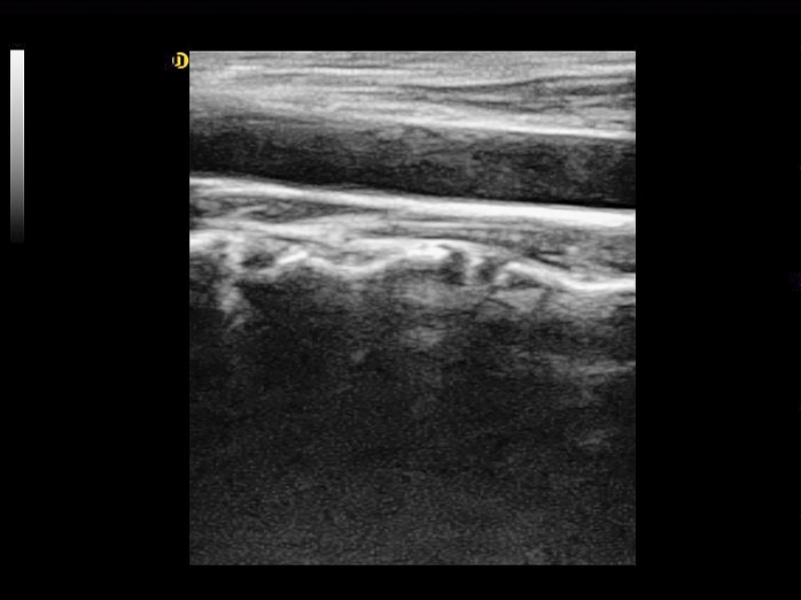

クリアフィルター

スペックル低減イメージング (SRI)